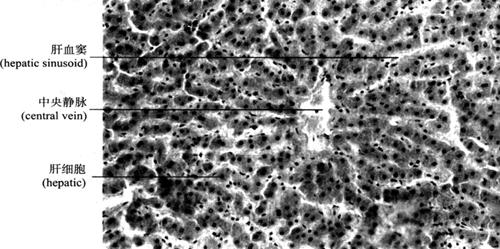

2.肝的组织结构 肝表面有致密结缔组织被膜(也称Glisson囊)。在肝门处,此结缔组织纤维囊特别发达,并包绕门静脉、肝动脉和肝管的分支形成Glisson鞘,进入肝内,成为Glisson系统,将肝实质分隔成许多肝小叶。肝小叶(hepatic lobule)是肝脏的结构和功能单位,呈多面形棱柱体,长约2mm,宽约1mm。其长轴中央有肝静脉的终末支中央静脉(central vein)穿过。成人肝脏约有50~100万个肝小叶。肝小叶主要结构为肝细胞和肝血窦。肝细胞以中央静脉为中心呈放射状排列,单排肝细胞组成立体板状结构,称肝板(hepatic plate)(图9-40),相邻肝板互相吻合成网状;肝血窦位于肝板之间,通过肝板上的孔洞互相通连;相邻肝细胞接触面,质膜内陷成沟,两沟对合成微细管道,称胆小管(bile canaliculi),以盲端起始于中央静脉附近,在肝板内互相连接成网。肝细胞分泌的胆汁经胆小管汇入肝小叶周边的小叶间胆管(interlobularbile ducts)。在肝组织切片中,肝板的断面呈索状,称肝索(hepatic cord)(图9-41)。

图9-41 肝脏(200×)

(2)肝血窦(hepatic sinusoid):是位于肝板之间的窦状毛细血管,来自小叶间动、静脉终末支的血液经其汇入中央静脉。肝血窦壁由一层有孔内皮细胞组成,通透性较大,有利于肝细胞与血液间物质交换。窦内有许多形状不规则的巨噬细胞(macrophase),称枯否细胞(Kupffer cell)(图9-43),具有变形运动和吞噬功能,可清除血液内异物、细菌、衰老的红细胞。由于其数量大,分布在血窦内重要部位,构成机体重要防御屏障,尤其在抗肝癌作用方面受到重视。体外培养的Kupffer细胞受肿瘤抗原刺激后,体积增大,Fc受体增加,与肿瘤细胞贴附力增强,细胞分泌肿瘤坏死因子(TNF)增多,可杀伤和破坏肿瘤细胞,而不影响正常细胞。

图9-43 肝索与肝血窦(400×)